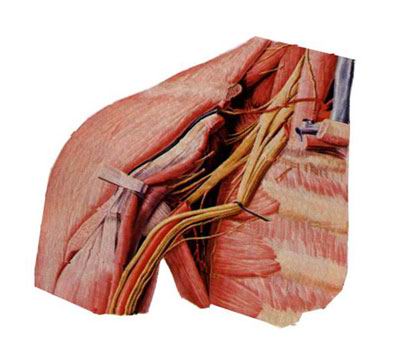

2.臂丛

由第5~8颈神经前支、第1胸神经部分前支组成。穿斜角肌间隙,经锁骨后方入腋窝。分为外侧束、内侧束和后束。主要分支有:

(1)肌皮神经

由臂丛外侧束发出,沿肱二头肌深面下行,肌支支配前臂前群肌,皮支布于前臂前外侧半皮肤。

(2)正中神经

由来自于外侧束和内侧束的两个根合成,伴肱动脉下行至肘窝,在前臂前群肌深浅两层之间下降,经腕管入手掌。肌支主要支配前臂大部屈肌,皮支主要布于手掌桡侧三个半指及相应手掌皮肤。损伤后表现为“猿手”。

(3)尺神经

由臂丛内侧束发出,初伴肱动脉下降,继而绕过尺神经沟至前臂伴尺动脉入手掌。肌支主要支配前臂尺侧一个半屈肌(尺侧腕屈肌和指深肌尺侧半,简称一尺半深)和大多数手肌。皮支主要分布手掌尺侧一个半指、手背尺侧二个半指及相应手掌、手背皮肤。肱骨髁上骨折最易损伤尺神经,表现为“爪形手”。

(4)桡神经

由臂丛后束发出,沿桡神经沟下行至前臂及手背。肌支主要支配臂和前臂后群肌及前群的肱桡肌。皮支主要布于手背桡侧两个半指及相应手背皮肤。损伤后表现为“垂腕”。

(5)腋神经

由臂丛后束发出,绕肱骨外科颈行向后外,肌支支配三角肌,皮支布于肩部皮肤。损伤后表现为“方肩”。